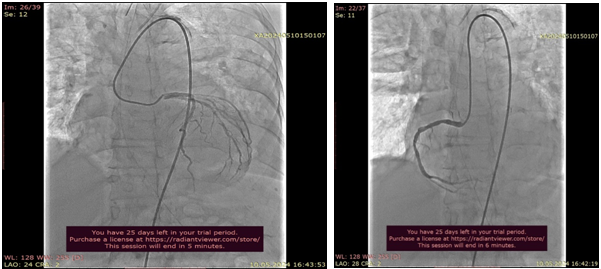

TAVİ: The procedure was performed under general anesthesia. A temporary pacemaker was implanted via left femoral vein. A pigtail catheter was placed in the noncoronary cusp, and a stiff Confida wire was placed inside the left ventricle. The 29 mm Medtronic Evolute Valve was carefully advanced until the aortic annulus, positioned and deployed under rapid ventricular pacing. The deployment was carried out in an extremly slow and careful, in a single attempt. After deployment,rapid ventricular pacing stimulation was kept. Hemodynamically significant leakage and gradient were not observed in the valve.

There was immediate improvment in hemodynamics following valve deployment.The diastolic pressure was 24 mmHg and it recovered to 58 mmHg immediately post-deployment. During 1h follow-up after procedure urine output was 150 ml/h. We stopped furosemid infusion and after that urine output was 100-150 ml/ per h.After 1 day inotrop support we stopped inotropic agents also and daily blod pressure interval 115-125/ 55-60 mmHg.